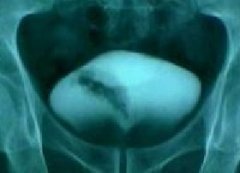

四、X线造影检查:

X线造影检查是膀胱癌的检查方法,通过造影可了解膀胱充盈情况和肿瘤浸润的范围、深度。结合肾盂和输尿管造影可了解是否肾积水、输尿管浸润及浸润的程度等。